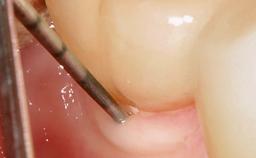

Occlusal Load—a Factor for Implant Failure?

In this case, Nicola Zitzmann describes the sudden loss of a previously well-osseointegrated implant that had been in healthy function for 5 years. The case includes recommendations for occlusion and function of implant restorations. A 74-year-old patient had received implant-fixed dental prostheses in the maxilla in 2008, and in the right mandible three years later. His tooth loss was mainly related to recurrent caries associated with hyposalivation as a potential side effect of his cholesterol-lowering medication.